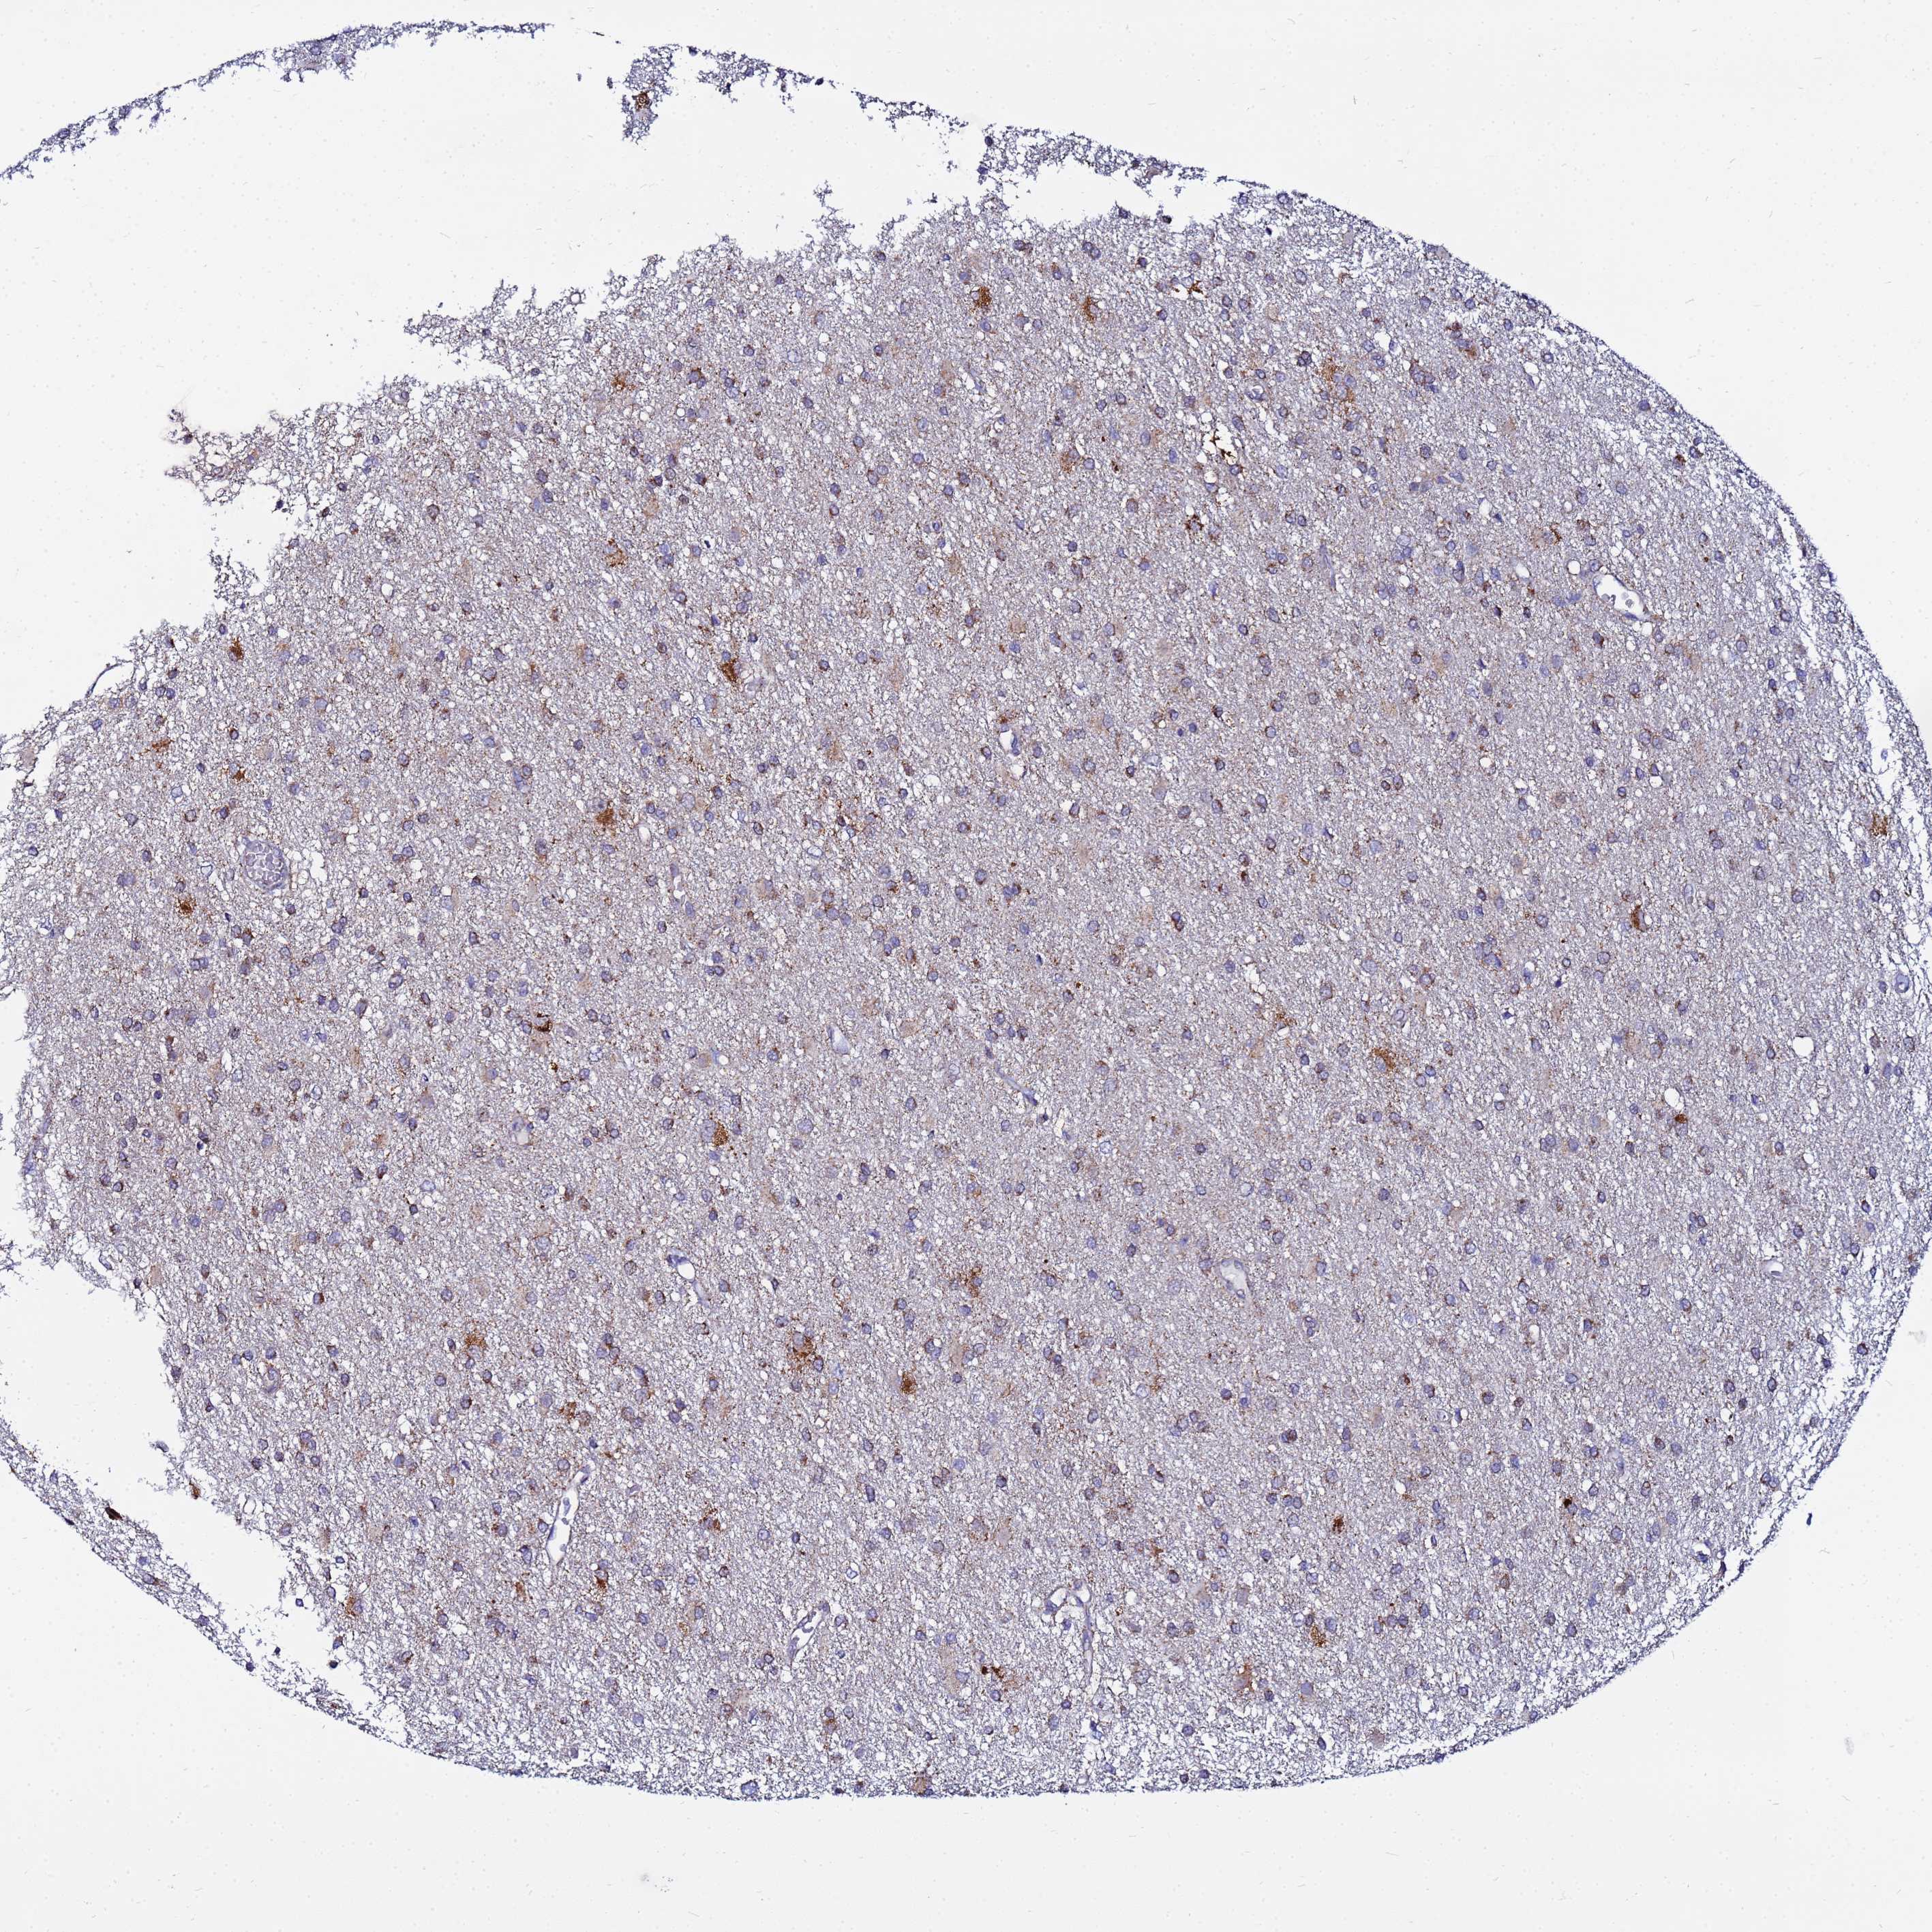

GLIOMA - Protein expressioni

A mouse-over function shows sample information and annotation data. Click on an image to view it in a full screen mode. Samples can be filtered based on level of antibody staining by selecting one or several of the following categories: high, medium, low and not detected. The assay and annotation is described here.

Note that samples used for immunohistochemistry by the Human Protein Atlas do not correspond to samples in the TCGA dataset.

Antibody stainingi

Antibody staining in the annotated cell types in the current human tissue is reported as not detected, low, medium, or high, based on conventional immunohistochemistry profiling in selected tissues. This score is based on the combination of the staining intensity and fraction of stained cells.

Each image is clickable and will lead to virtual microscopy that enables deeper exploration of all samples and also displays staining intensity scores, fraction scores and subcellular localization as well as patient and tissue information for each sample.

Antibody HPA042145

Antibody HPA044987

Antibody CAB045971

Antibody CAB045972

Staining

High

Medium

Low

Not detected

Intensity

Strong

Moderate

Weak

Negative

Quantity

>75%

75%-25%

<25%

None

Location

Nuclear

Cytoplasmic/membranous

Cytoplasmic/membranous,nuclear

Glioma, malignant, Low grade

Glioma, malignant, High grade